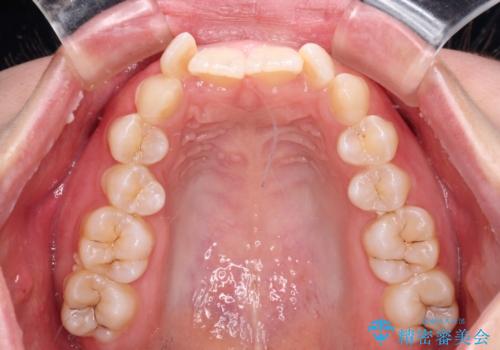

- 上下前歯のデコボコを気にして来院された患者様です。

口元の突出感はあまりなかったものの、デコボコを非抜歯で改善すると出っ歯になる可能性があるため、上下左右の第一小臼歯4本を抜歯し、ワイヤー装置にて矯正治療を行うこととしました。